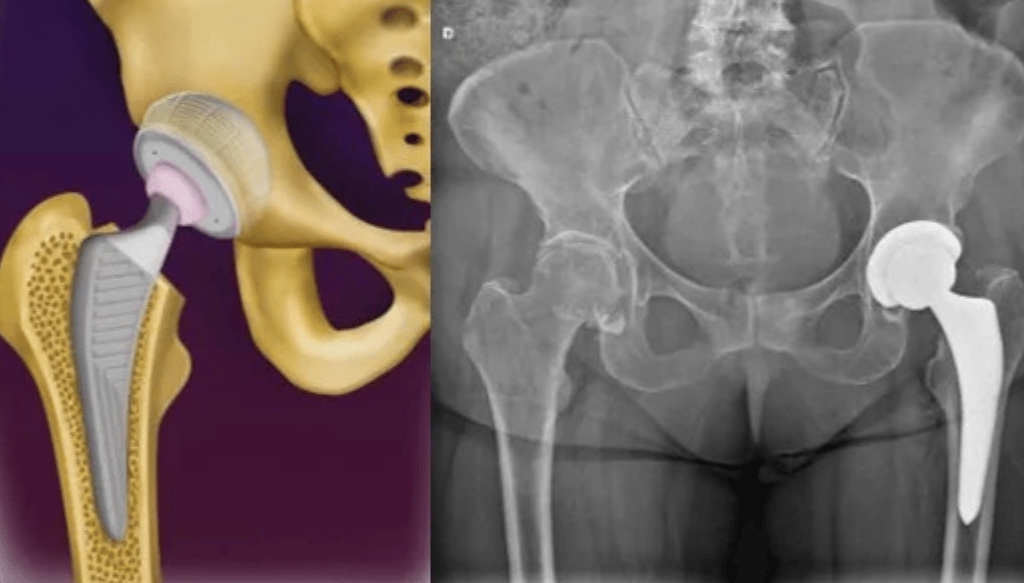

A artrose do quadril é uma condição degenerativa da articulação, que cursa com o desgaste da cartilagem, fazendo com que o paciente apresente dor ao andar e movimentar o quadril.

Faz-se o diagnóstico com RX e Ressonância Magnética.

O tratamento se inicia com medicações analgésicas, perda de peso e Fisioterapia. No entanto, pode-se realizar infiltração com ácido hialurônico na articulação caso o paciente persista com dor na coxa ou dor no quadril.

Com o avanço dos materiais utilizados na cirurgia e nas técnicas cirúrgicas, o paciente volta a ter uma vida normal, praticamente sem limitações após a cirurgia. As próteses mais modernas têm uma durabilidade de aproximadamente 25 anos, permitindo que mesmo pacientes mais jovens possam ser submetidos a essa cirurgia.

Faz-se o tratamento com a prótese de quadril em casos avançados, ou seja, em que houve colapso/retificação da cabeça femoral ou quando já existe artrose instalada.

Já em casos avançados, realiza-se o tratamento com a cirurgia de prótese do quadril, na qual substitui-se a articulação com desgaste por uma articulação metálica, que irá reproduzir os movimentos e funções de um quadril normal.